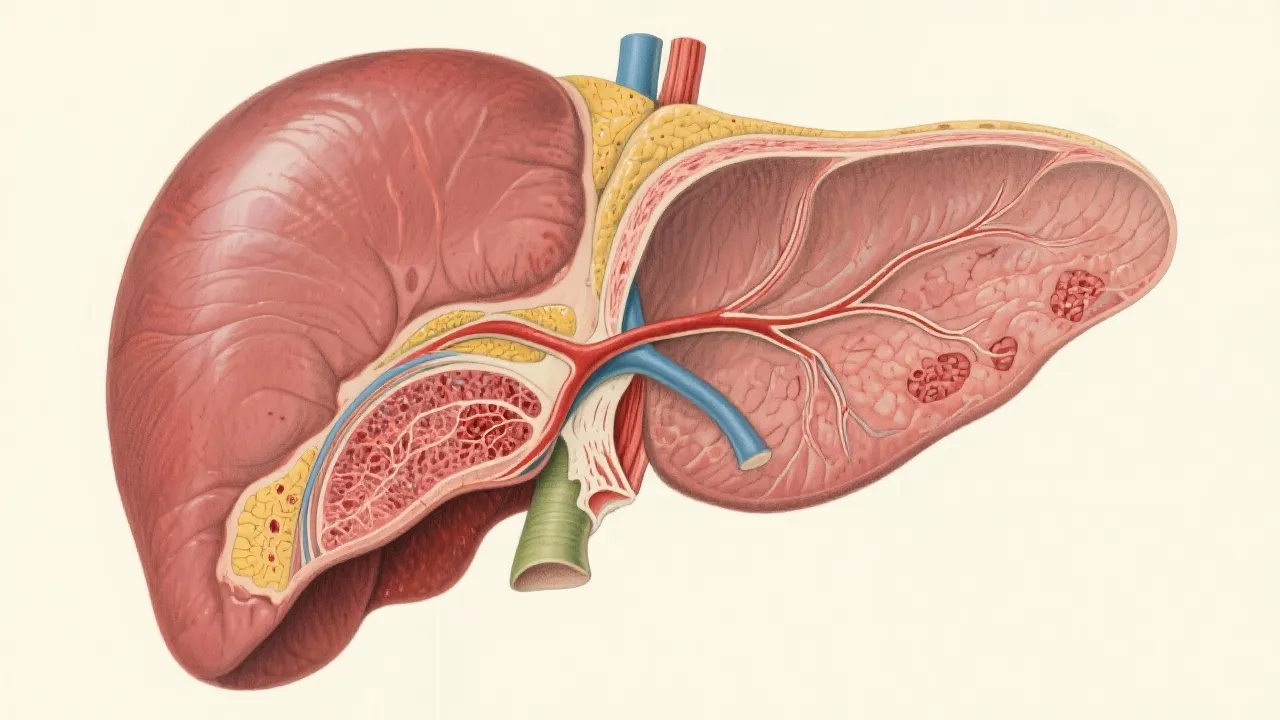

NAFLD-related HCC is a growing concern in medical circles, as Non-Alcoholic Fatty Liver Disease (NAFLD) increases globally, contributing to hepatocellular carcinoma (HCC) incidence. As weight gain and poor dietary habits become prevalent, so do liver diseases, turning the spotlight on their progression to liver cancer. This article delves into the mechanisms, risk factors, and prevention strategies surrounding this healthcare challenge.

Non-Alcoholic Fatty Liver Disease (NAFLD) is a condition characterized by excess fat build-up in the liver not caused by alcohol consumption. As modern lifestyles lean towards sedentarism and high-calorie diets, the incidence of NAFLD continues to rise, amplifying healthcare burdens globally. Alarmingly, NAFLD can progress to more severe liver diseases, including Non-Alcoholic Steatohepatitis (NASH), leading ultimately to hepatocellular carcinoma (HCC). Recent studies estimate that NAFLD affects approximately 25% of the global population, highlighting a significant public health challenge. In particular, the rise of obesity and diabetes, which are closely linked to NAFLD, underlines the urgency to address underlying lifestyle factors to mitigate this complex condition.

In patients with NAFLD, the journey toward liver cancer involves a series of progressive liver damage stages. Initially, fat accumulation in the liver causes inflammation and fibrosis—known as NASH, which over time can progress to cirrhosis. As this condition develops, the liver undergoes significant cellular changes. When the liver is inflamed, it activates immune responses that can lead to further liver damage and fibrogenesis. Consequentially, cirrhosis presents an optimal environment for the development of HCC due to chronic inflammation and the regenerative drive of liver cells, which increases the mutation risk. Other contributing factors include oxidative stress and the release of pro-inflammatory cytokines, promoting a microenvironment that favors cancerous growth. Research continues to unveil genetic and environmental interactions involved in the pathogenic processes leading to HCC, signaling an evolving understanding in the field.